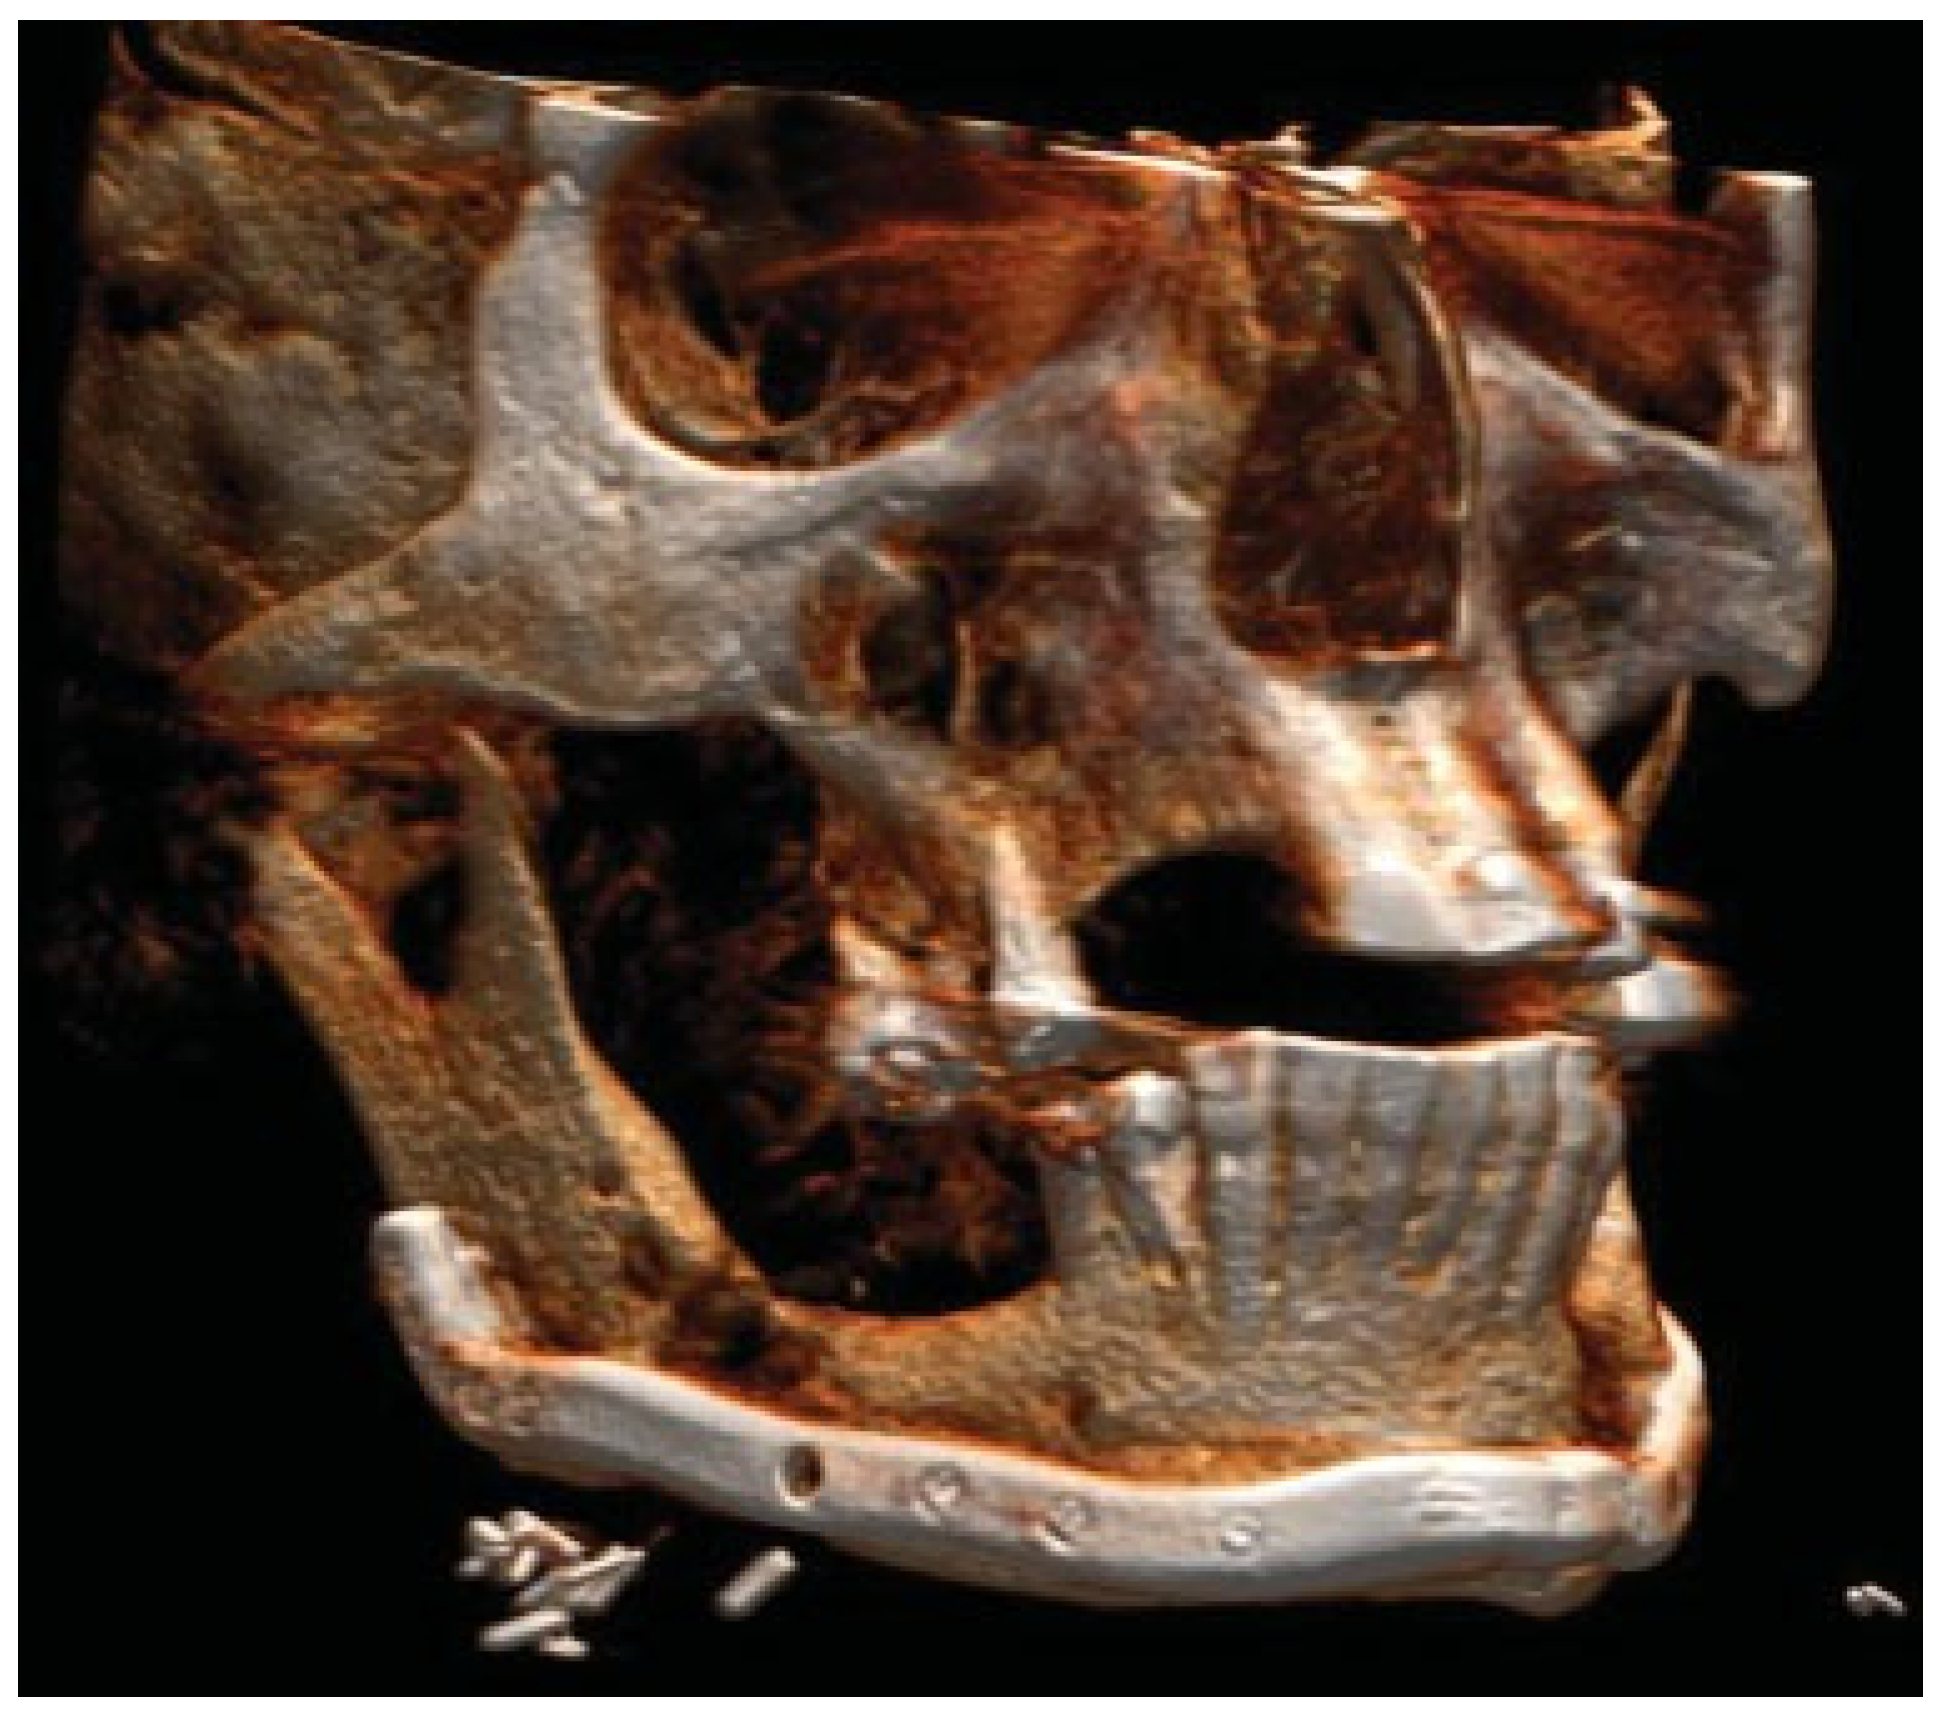

Figure 3.

Patient developed infections with oral mucosal fistulas in the fracture areas and an open bite. CBCT displays obvious anterior rotation of proximal segments and posterior rotation of the dentate part of mandible. Considerable muscle action creates new dislocation and is not counteracted by the inadequate osteosynthesis of the fractures.